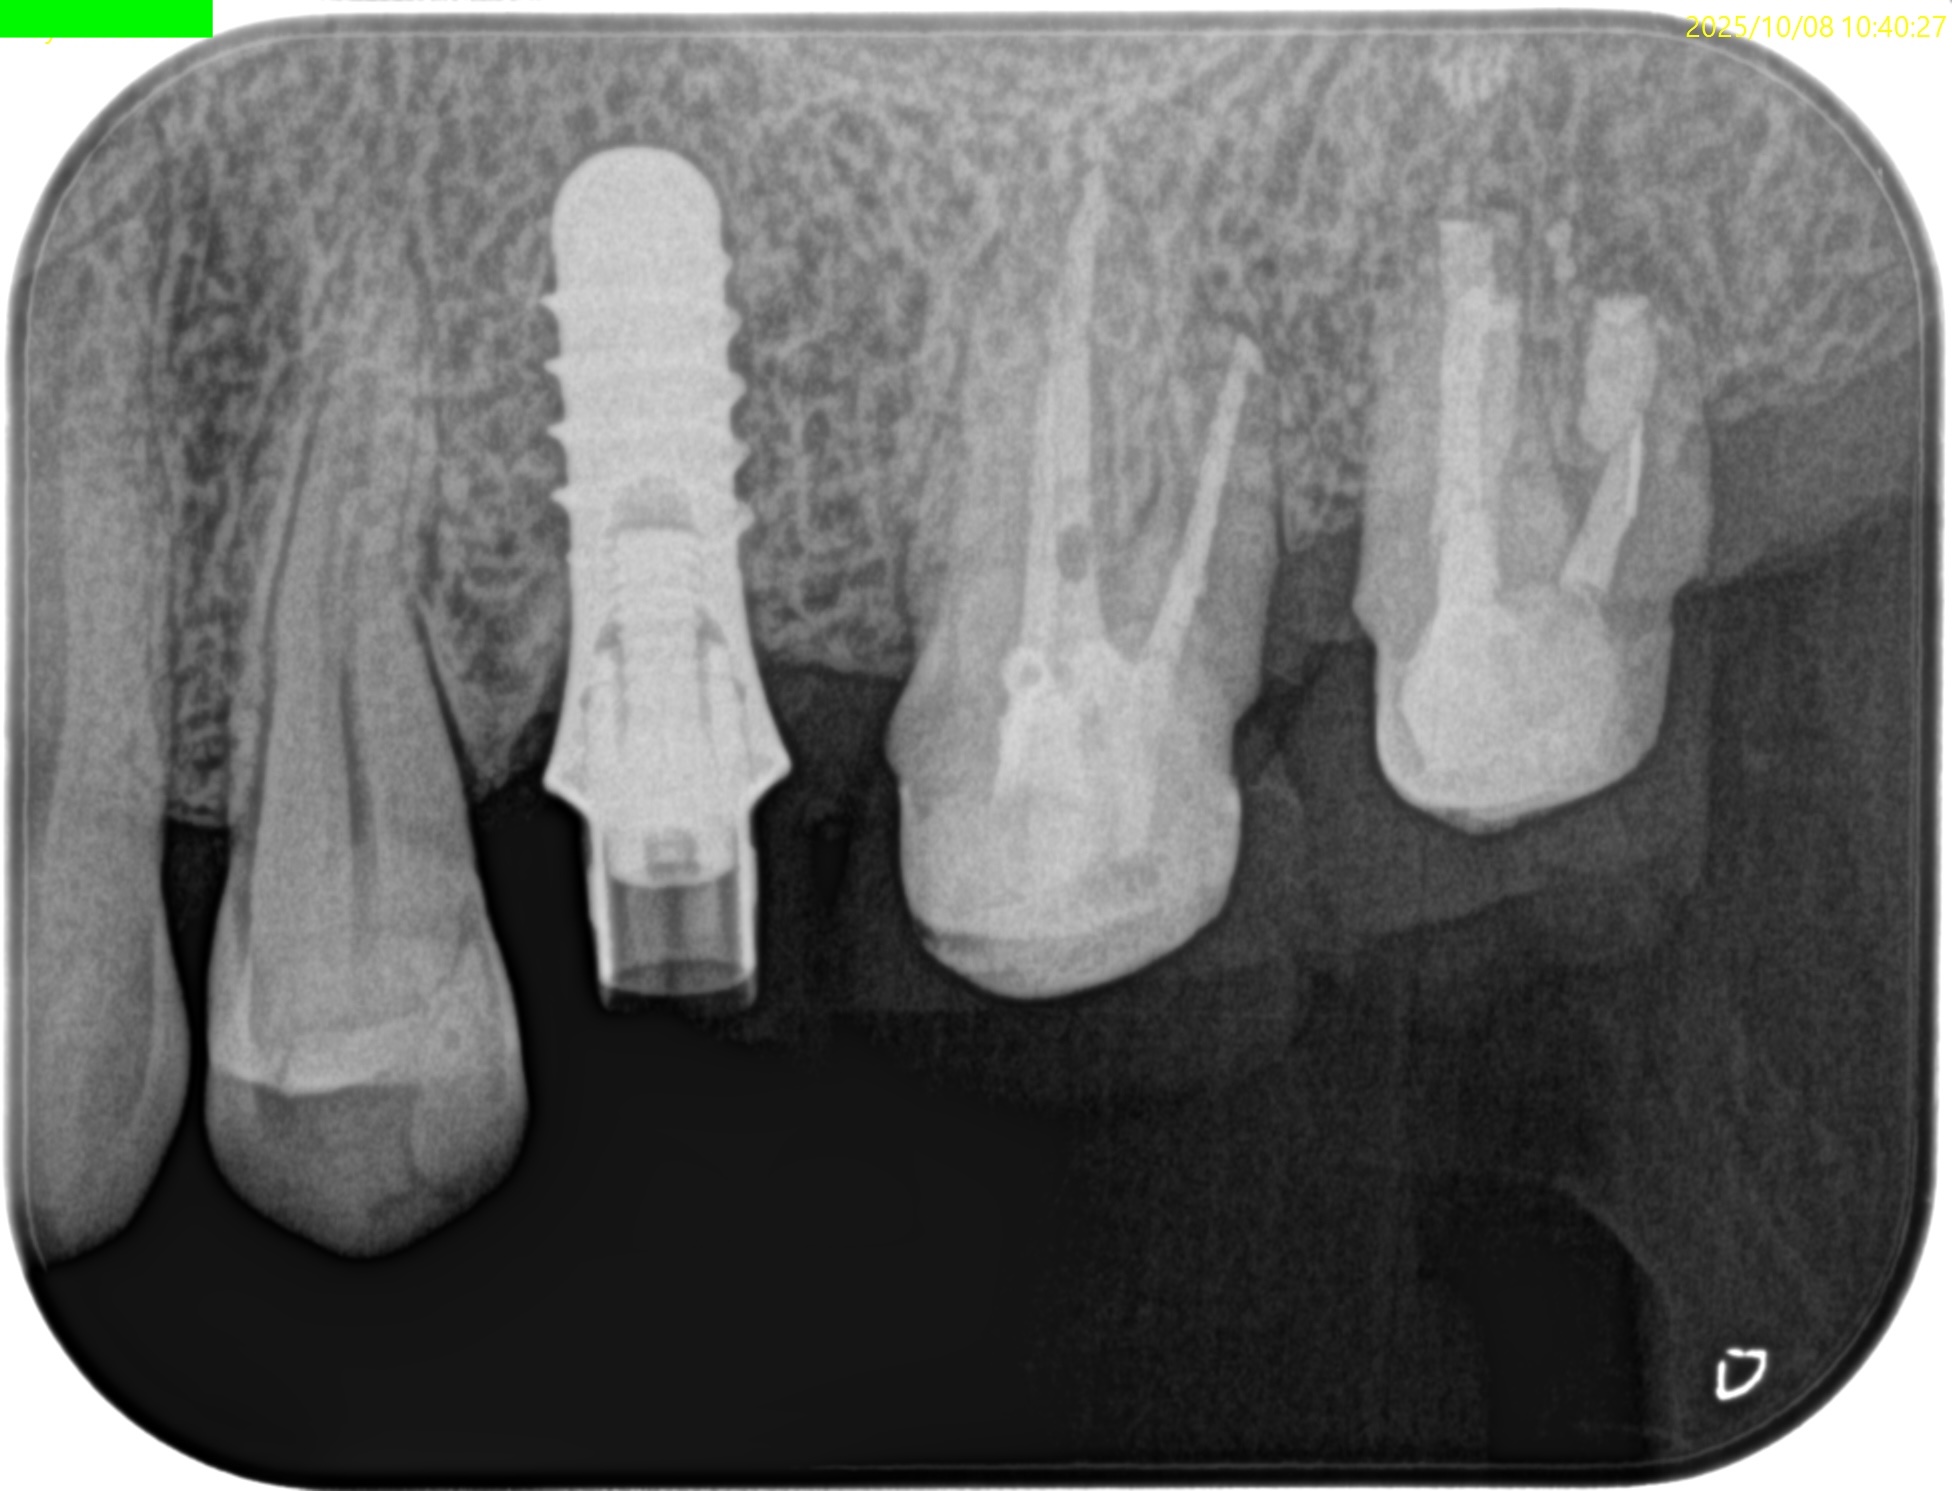

#15 Intentional Replantation 6M recall(2025.10.8)

術直後と比較した。

歯槽骨がだいぶ回復している。

最終補綴もOKだ。